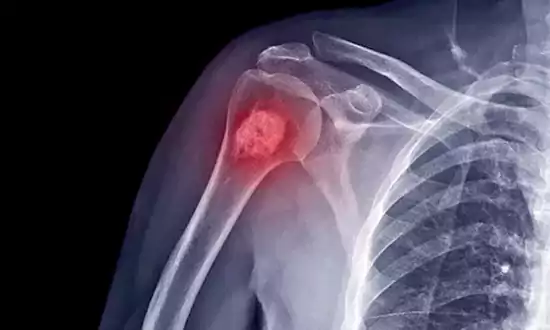

బోన్ సిస్ట్.. దీన్నే ఎముక తిత్తి అని అంటారు. ఎముక తిత్తి అనేది ఎముక సంబంధిత సమస్య, దీని గురించి కొంతమందికి మాత్రమే తెలుసు. ఇది చాలా అరుదైన వ్యాధి, కానీ ఎవరికైనా ఇది వచ్చినప్పుడు, వారి సమస్యలు విపరీతంగా పెరుగుతాయి. ఎముక తిత్తి అభివృద్ధి చెందినప్పుడు, ఆ ప్రాంతంలోని ఎముక నెమ్మదిగా కరిగిపోవడం ప్రారంభమవుతుంది. తరచుగా ఈ సమస్యను క్యాన్సర్తో రిలేటెడ్ గా పరిశీలిస్తారు. కానీ ఇది క్యాన్సర్ కు సంబందం లేని వ్యాధి.

ఈ వ్యాధి ప్రారంభం లక్షణాలు ప్రభావిత ప్రాంతంలో వివరించలేని నొప్పి,, ఎక్స్-కిరణాలు ఆ ప్రాంతంలో ఎముక సాంద్రత తగ్గినట్లు వెల్లడిస్తాయి. అదృష్టవశాత్తూ, ముందుగానే గుర్తిస్తే, దీనిని పూర్తిగా నయం చేయవచ్చు.

ఈ వ్యాధి తరచుగా ఆటలు ఆడే సమయంలో గాయాలు తగలడం జరిగినప్పుడు చేసే ఎక్స్-రే వాపు లేదా చిన్న బెణుకుల ద్వారా గుర్తించబడుతుంది.